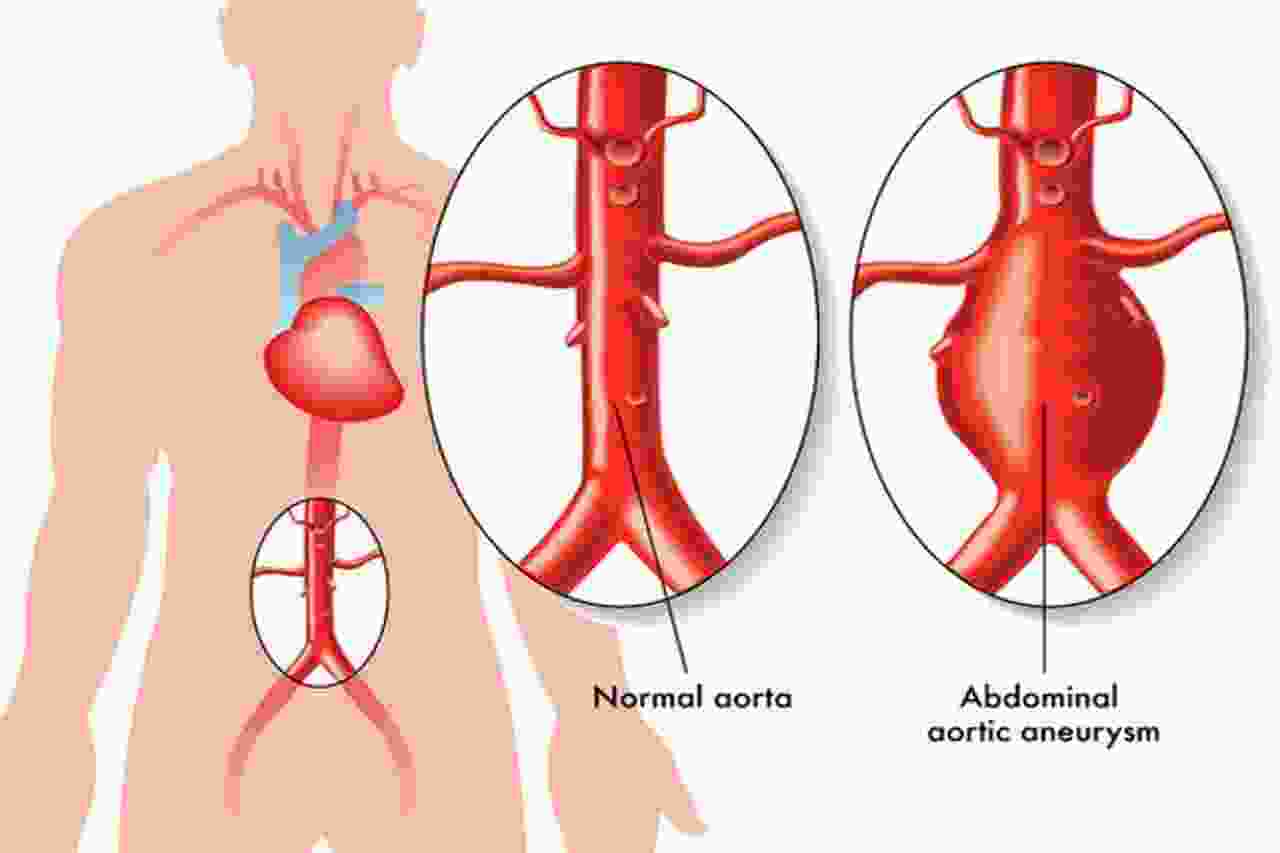

علاج توسع الشريان الأبهر

علاج توسع الشريان الأبهر والتمدد في جدار الشريان الرئيسي